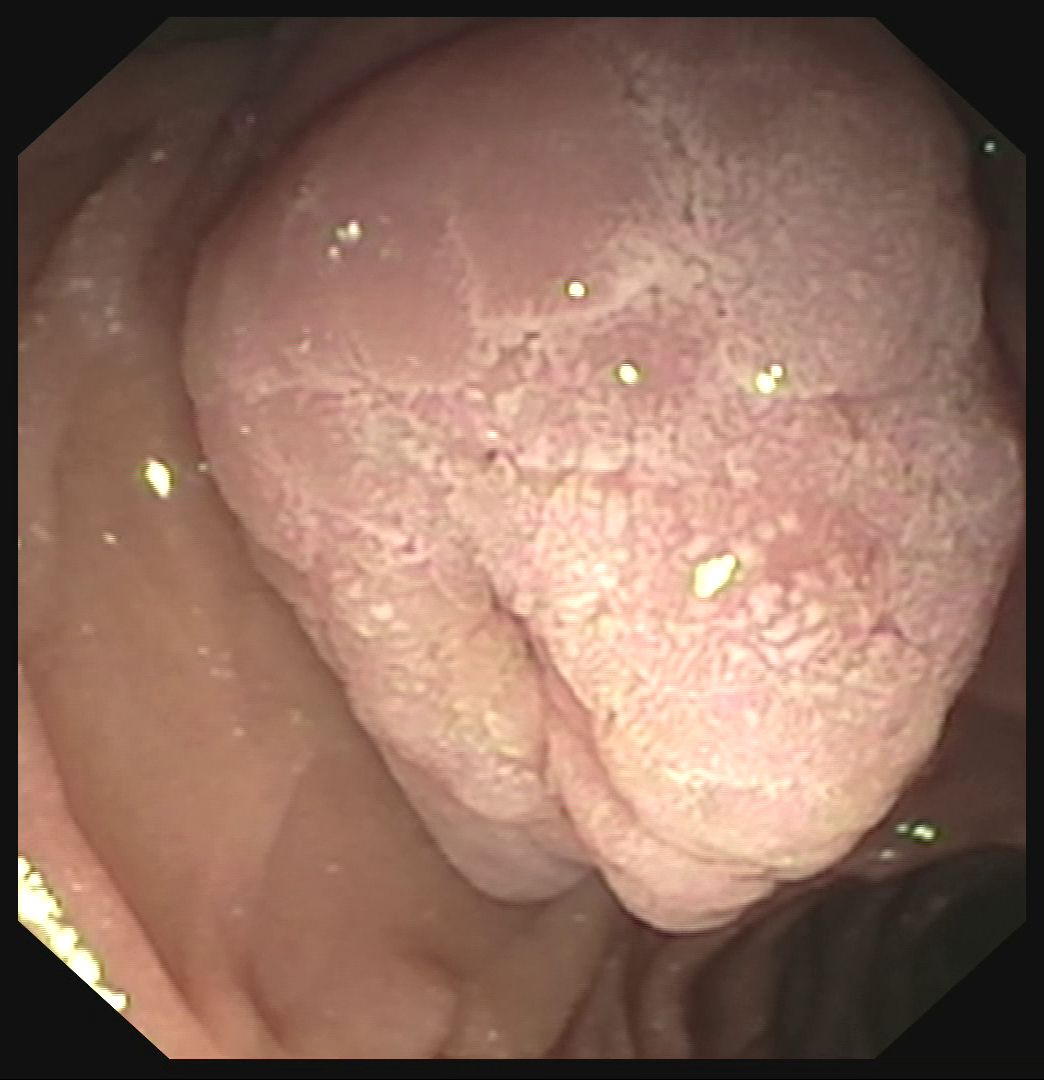

realizar un ampulectomía endoscópica. La duodenoscopia confirma la presencia de

una lesión papilar de unos 25-27 mm, con bordes bien definidos, sin ulceración

ni friabilidad, aunque en la colangiografía se aprecia un pequeño crecimiento

intraductal en el borde medial, inferior a 10 mm. Se opta por resección endoscópica mediante